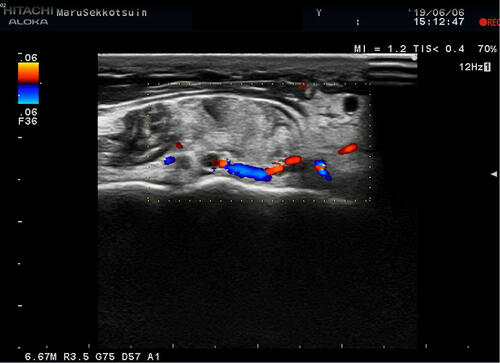

痛風echo.jpg

こればっかりは再度、血液検査を行わないと根本治療にはならないですが、

患者さまのお話を聞くと「痛風発作」に間違いないと思います。。